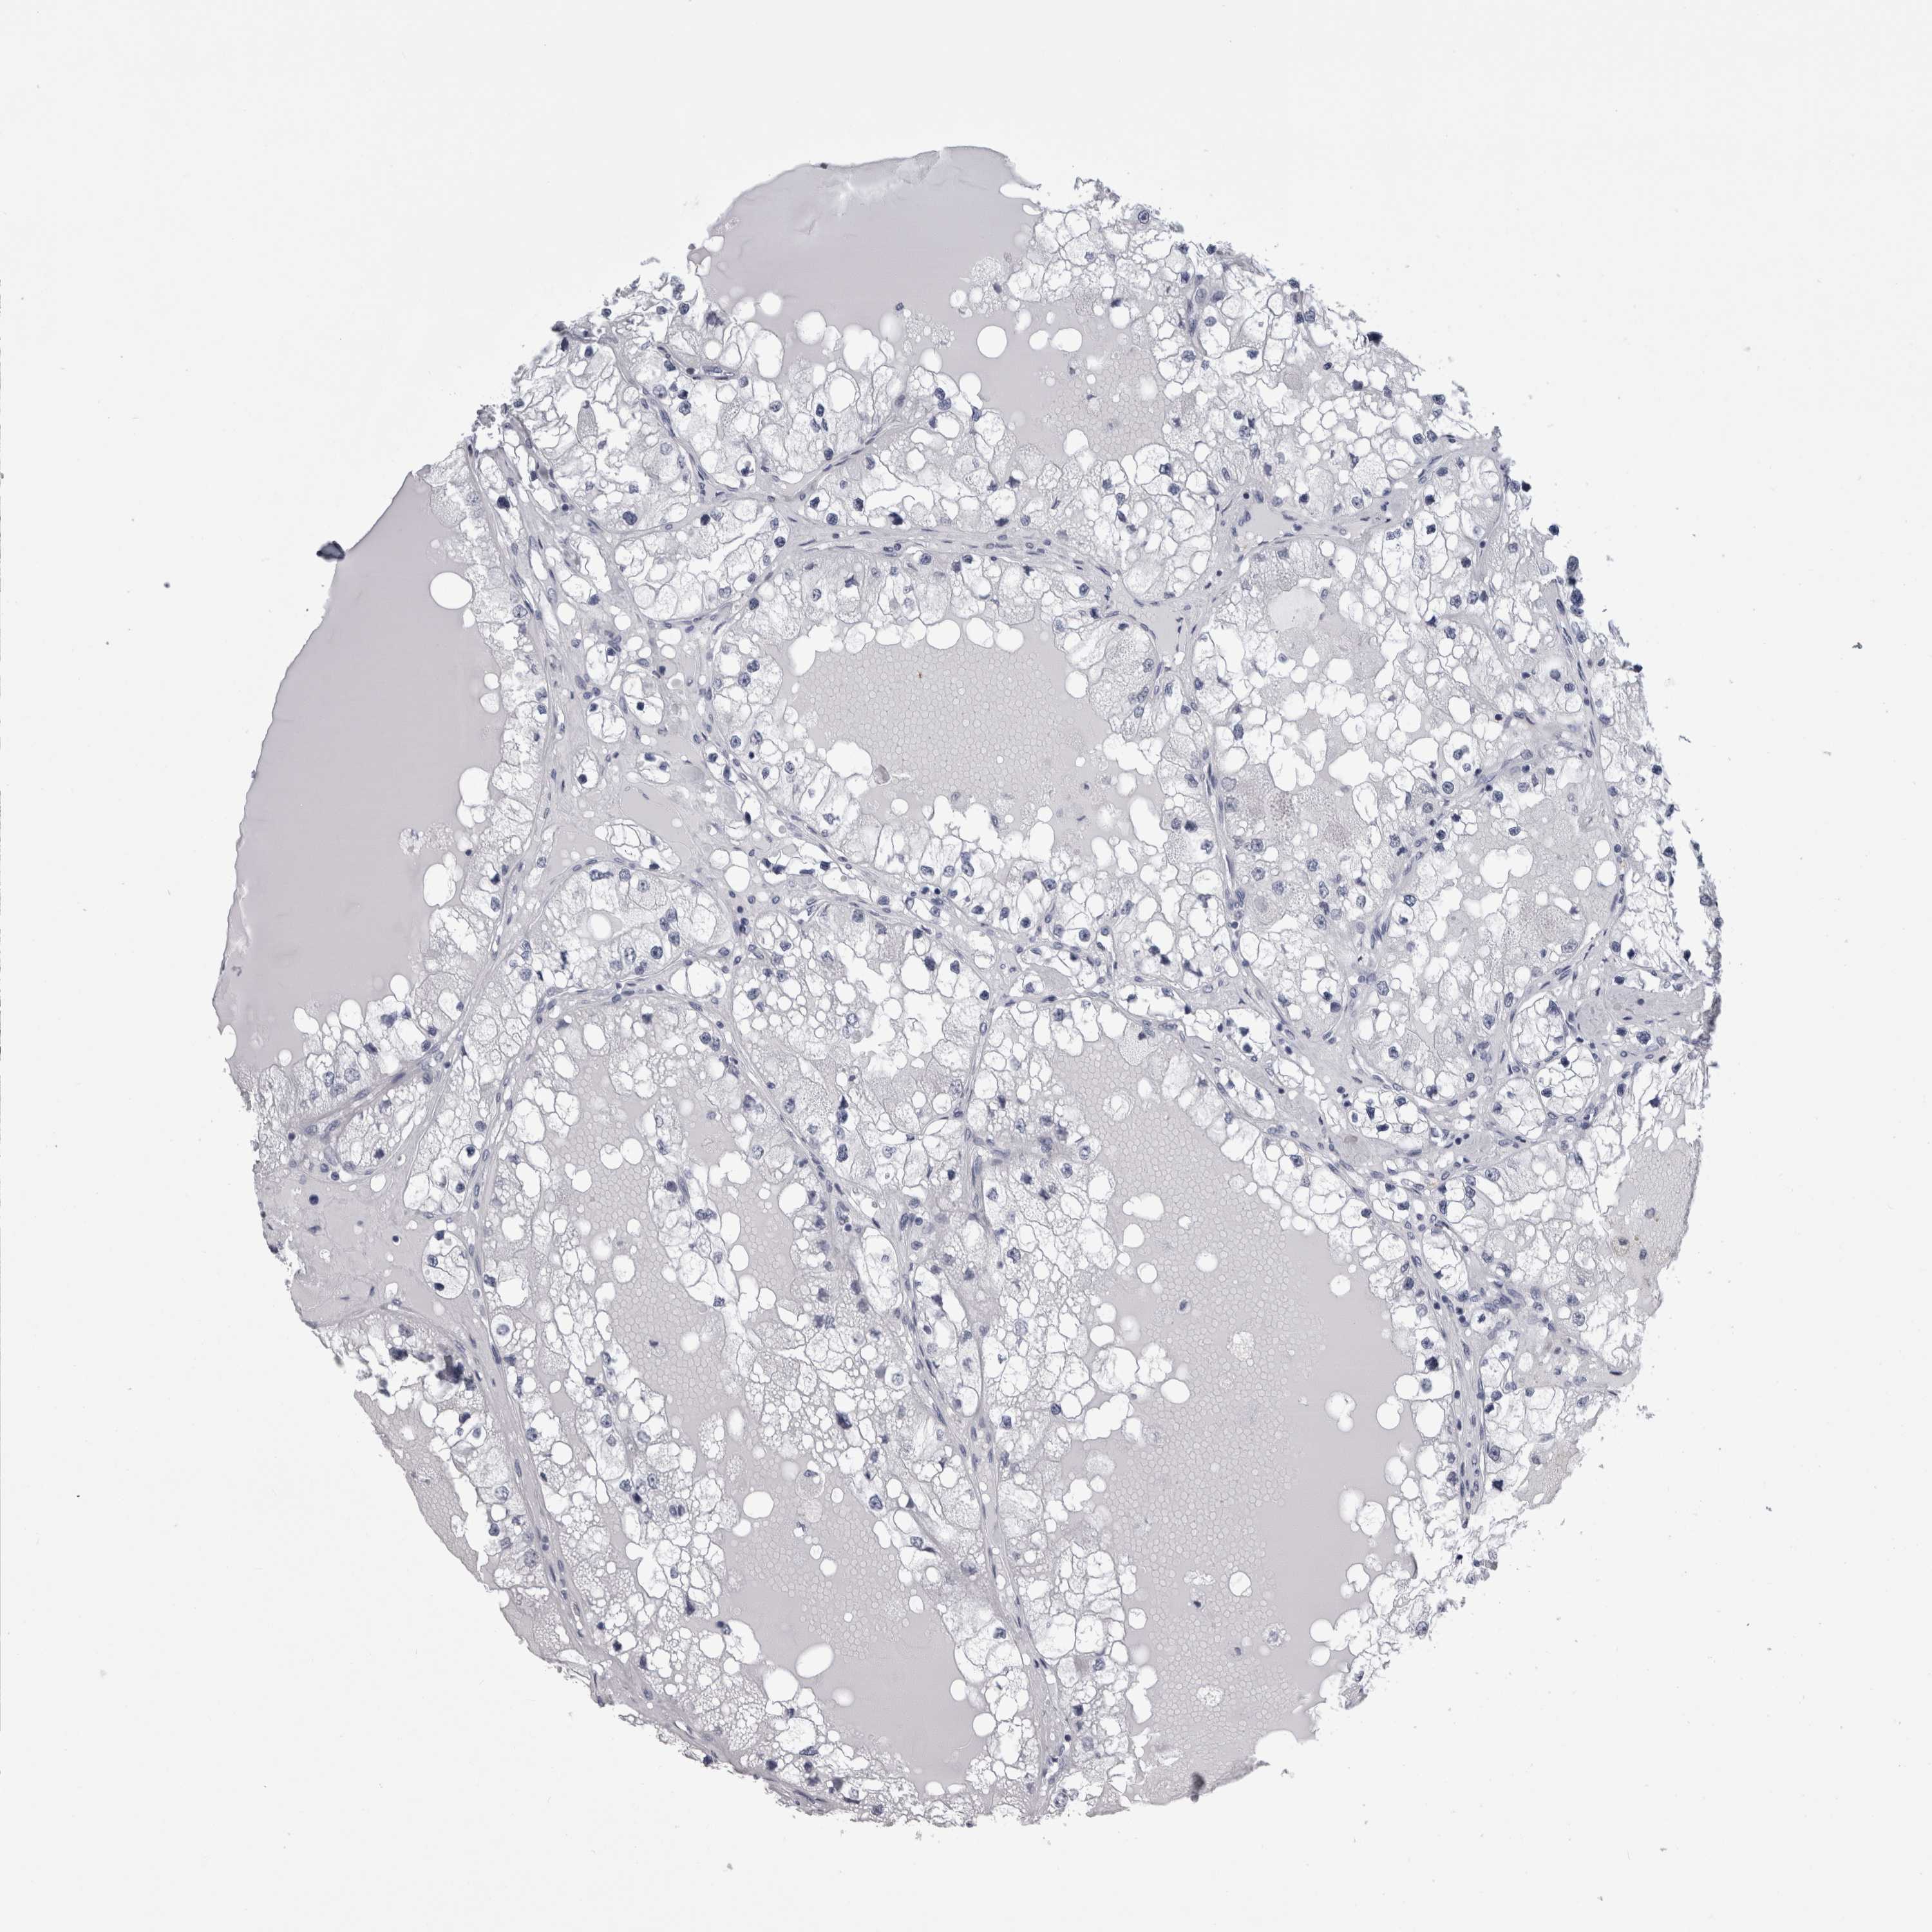

KIDNEY RENAL CLEAR CELL CARCINOMA (TCGA) - Interactive survival scatter ploti

The Survival Scatter plot shows the clinical status (i.e. dead or alive) for all individuals in the patient cohort, based on the same data that underlies the corresponding Kaplan-Meier plots. Patients that are alive at last time for follow-up are shown in blue and patients who have died during the study are shown in red.

The x-axis shows the expression levels (FPKM) of the investigated gene in the tumor tissue at the time of diagnosis. The y-axis shows the follow-up time after diagnosis (years). Both axes are complimented with kernel density curves demonstrating the data density over the axes. The top density plot shows the expression levels (FPKM) distribution among dead (red) and alive patients (blue). The right density plot shows the data density of the survived years of dead patients with high and low expression levels respectively, stratified using the cutoff indicated by the vertical dashed line through the Survival Scatter plot. This cutoff is automatically defined based on the FPKM cutoff that minimizes the p-score. The cutoff can be changed by dragging the vertical line or by entering a cutoff value in the square labeled "Current cut-off".

Under the Survival Scatter plot the p-score landscape (black curve; left axis) is shown together with dead median separation (red curve; right axis). Dead median separation is the difference in median mRNA expression between patients who have died with high and low expression, respectively. It is calculated as follows: median FPKM expression of dead patients with high expression - median FPKM expression of dead patients with low expression. This is intended to aid the user in visually exploring custom cutoffs and the associated p-scores and dead median separation.

Individual patient data is displayed and can be filtered by clicking on one or more of the category buttons on the top of the page. Categories describing expression level and patient information include: high, low, alive, dead, female, male and tumor stages. The scale of the x-axis can be toggled between linear and log-scale by clicking on the "x log" button. Mouse-over function shows TCGA ID, patient information and mRNA expression (FPKM) for each patient.

& Survival analysisi

Kaplan-Meier plots summarize results from analysis of correlation between mRNA expression level and patient survival. Patients were divided based on level of expression into one of the two groups "low" (under cut off) or "high" (over cut off). X-axis shows time for survival (years) and y-axis shows the probability of survival, where 1.0 corresponds to 100 percent.

ALDH8A1 is potential prognostic, high expression is favorable in Kidney Renal Clear Cell Carcinoma (TCGA)

Best expression cut offi

Based on the FPKM value of each gene, patients were classified into two groups and association between prognosis (survival) and gene expression (FPKM) was examined. The best expression cut-off refers the FPKM value that yields maximal difference with regard to survival between the two groups at the lowest log-rank P-value. Best expression cut-off was selected based on survival analysis .

When clicking on this number, the vertical dashed line indicating cut-off, the interactive survival plot, and the Kaplan-Meier curve will be adjusted to show results based on the best expression cut-off.

: 44.83

P scorei

Log-rank P value for Kaplan-Meier plot showing results from analysis of correlation between mRNA expression level and patient survival.

N/A

TCGA RNA samplesi

RNA-seq data is reported as average FPKM (number Fragments Per Kilobase of exon per Million reads), generated by the The Cancer Genome Atlas (TCGA) .

Normal distribution across the dataset is visualized with box plots, shown as median and 25th and 75th percentiles. Points are displayed as outliers if they are above or below 1.5 times the interquartile range. FPKM values of the individual samples are presented next to the box plot.

Average pTPM 29.2

Number of samples 521